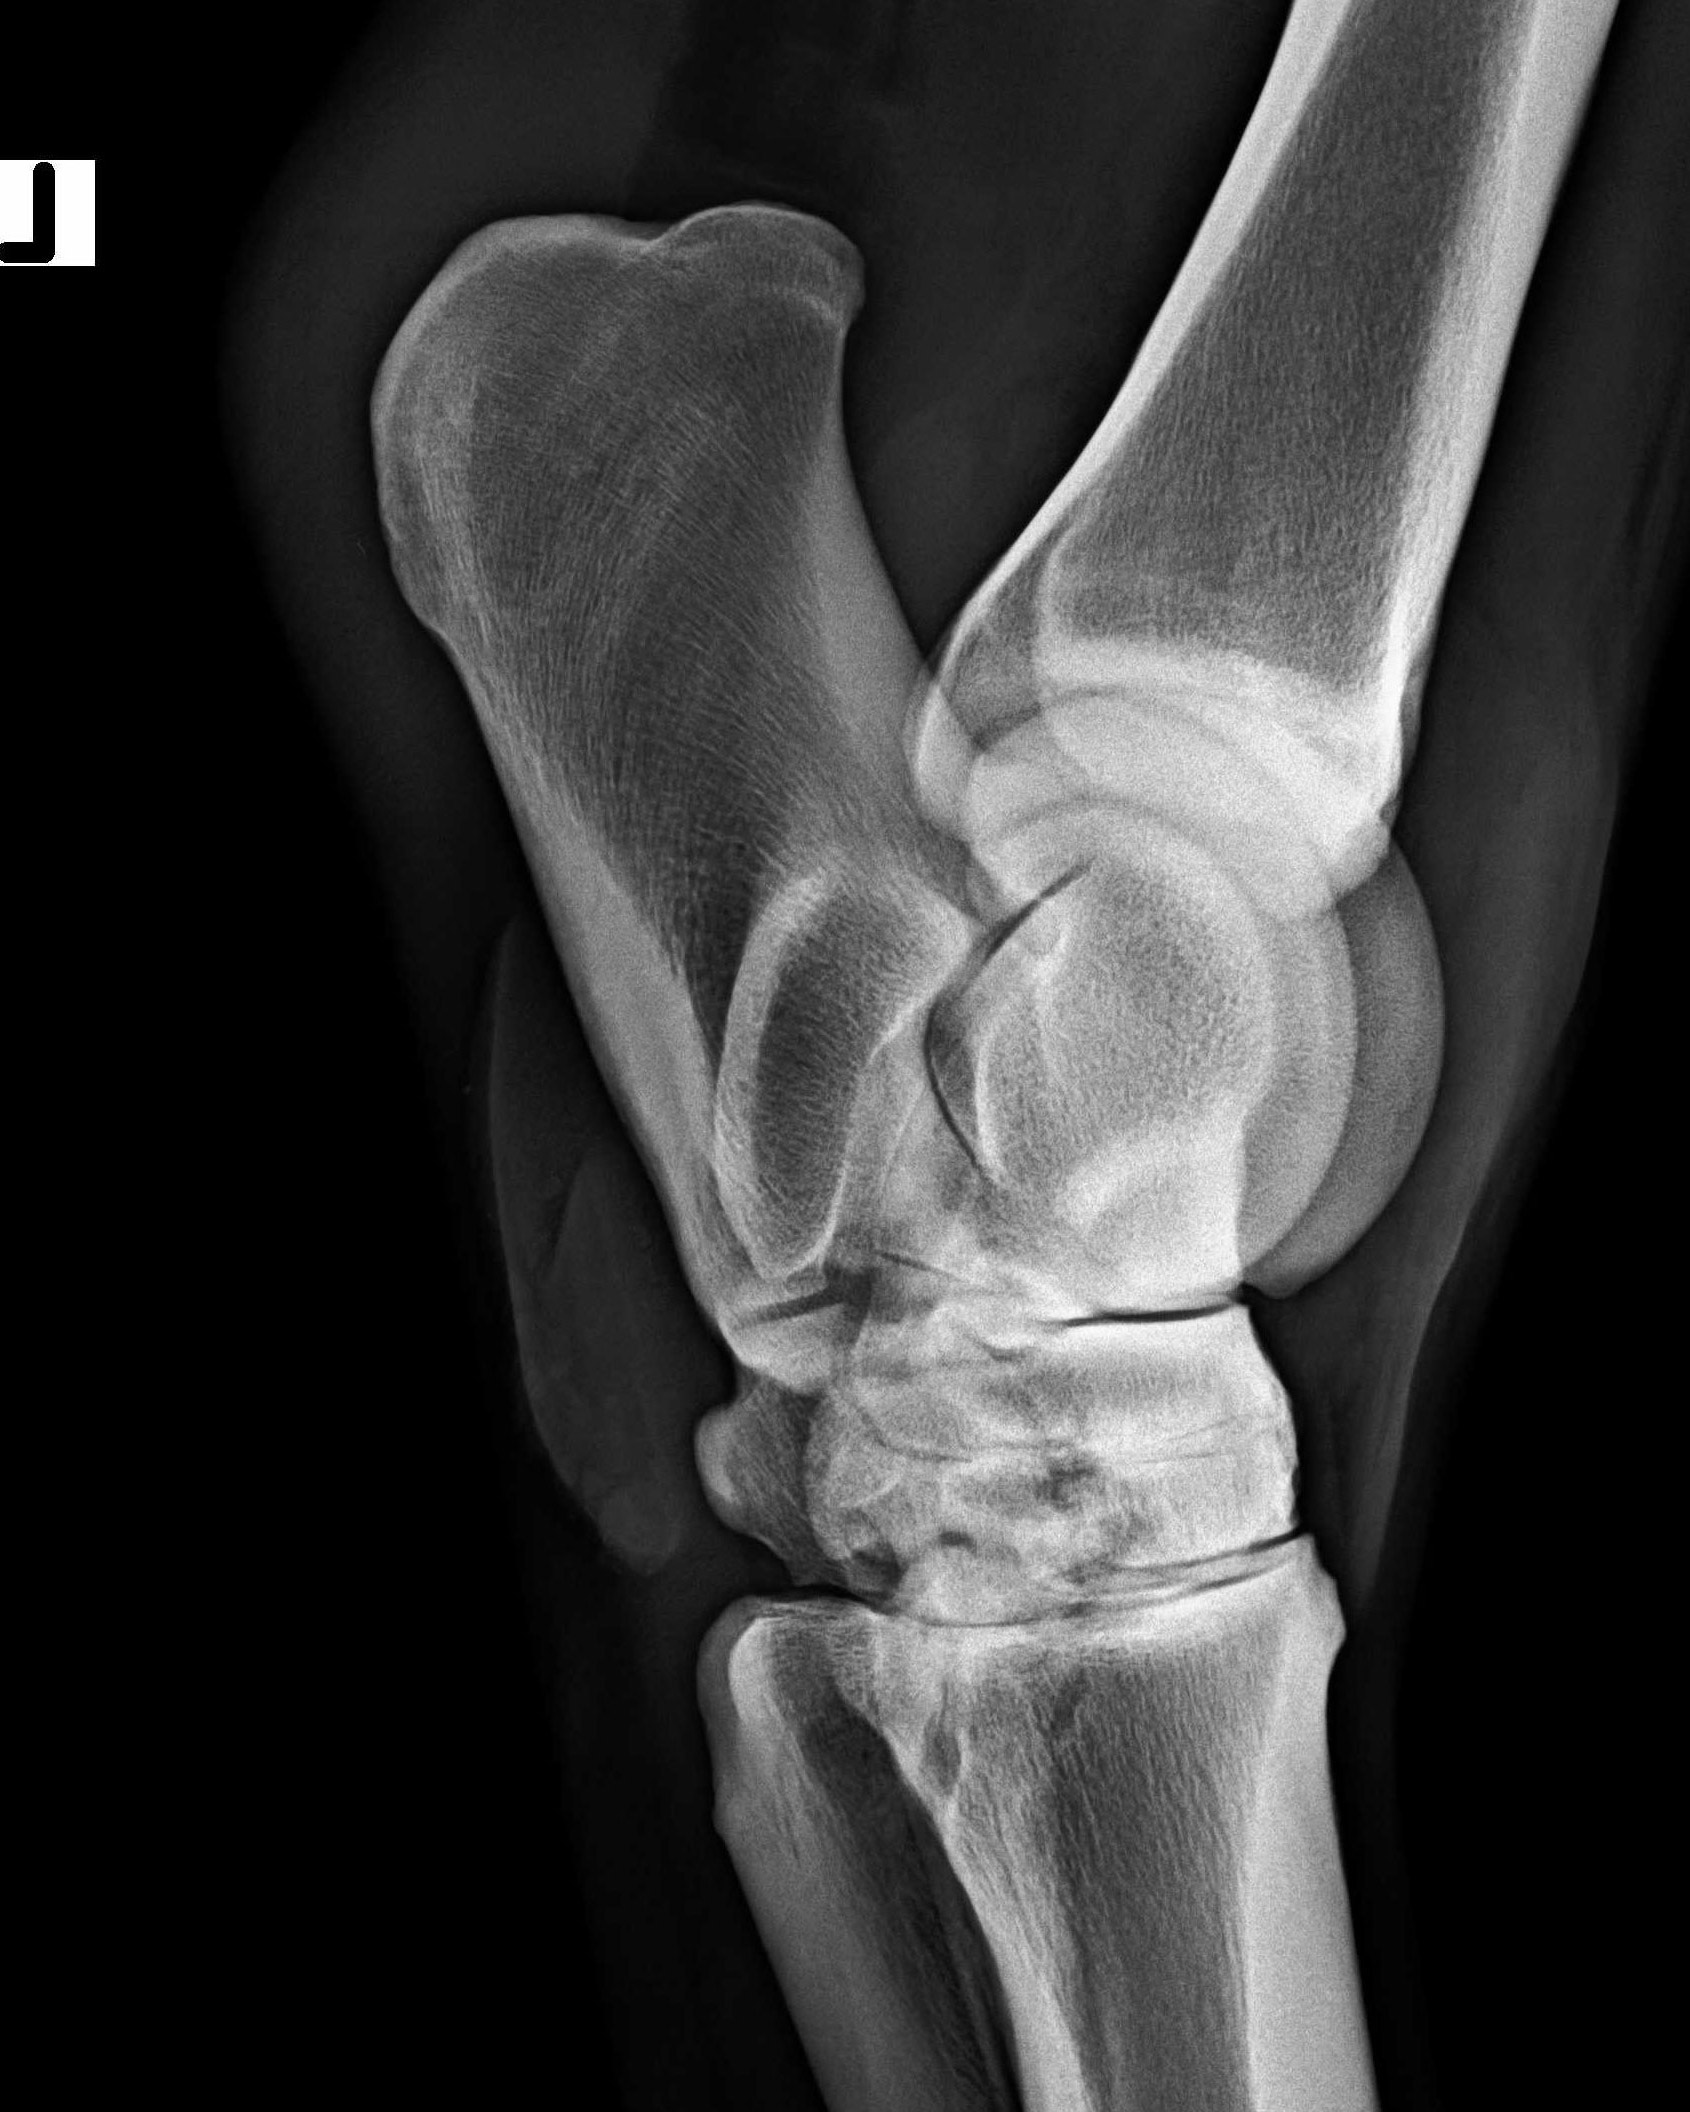

Sprunggelenk - 90°-Aufnahme